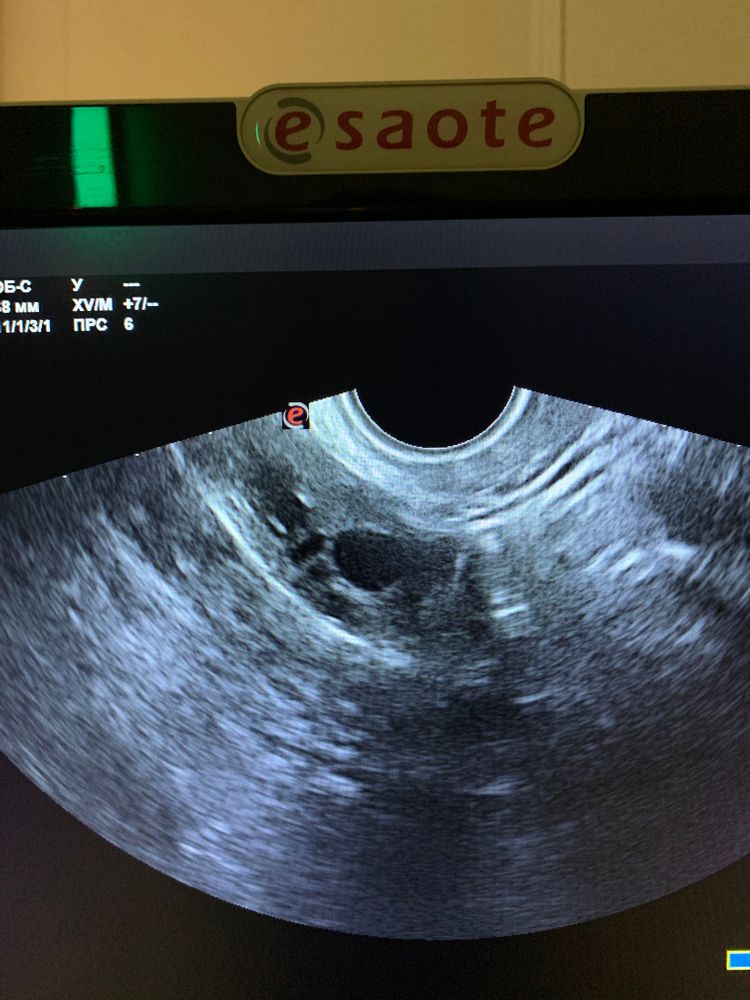

Жёлтое тело на узи после овуляции Гематометра, которая исчезла сама